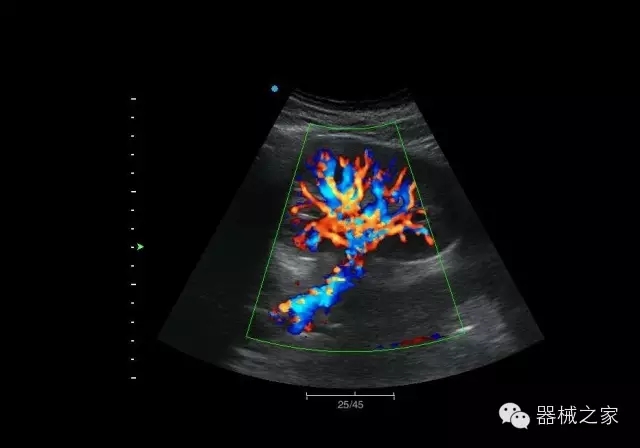

臨床圖片賞析

頸動脈頻譜